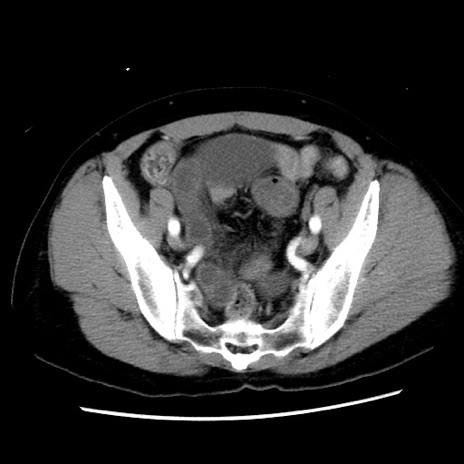

症例10(横断像)

【症例】 50歳代女性

【主訴】 腹痛

【現病歴】前日生レバーを食べた。今朝に排便あり。 昼前に突然発症の腹痛を生じ、当院救急外来を受診した。

【既往歴】 子宮筋腫にてで子宮全摘後

【身体所見】 意識清明、腹部:平坦、軟、下腹部やや左を中心に圧痛・反跳痛あり、筋性防御あり

【データ】WBC 7800、CRP 0.07